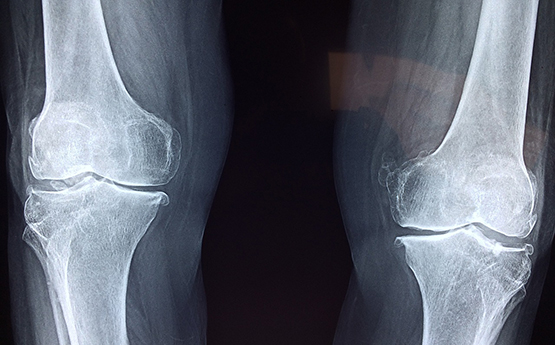

An x-ray of knees

Mae dadansoddiad dietegol a defnyddio cynhyrchion gwaed, gan ddefnyddio uwchsain a delweddu pelydr x deuol, yn gallu asesu strwythur a chyfansoddiad cyhyrau, iechyd y rhydwelïau, perfformiad corfforol ac amcangyfrif croniad braster. Drwy'r wybodaeth hon, gall unigolion ddysgu am oblygiadau mabwysiadu dietau penodol, ac o bosib, wella eu hiechyd, gan leihau dibyniaeth ar gamwybodaeth a thystiolaeth anecdotaidd.